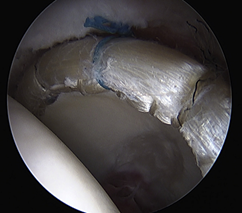

髋臼盂唇损伤的治疗方法包括保守治疗和手术治疗。保守治疗主要适应于症状较轻者,采取4周的卧床休息,逐渐进行肌力、本体感觉和负重练习,必要时可辅助止痛和理疗。但是,髋臼盂唇的血管分布相对匮乏,且与关节软骨通过移行区连接,一旦损伤后其自行愈合能力有限,应该早期予以手术治疗。目前,髋臼盂唇损伤的手术治疗的方法包括髋臼盂唇切除、髋臼盂唇缝合修补和髋臼盂唇重建。髋臼盂唇切除适应于较小的周缘或瓣状撕裂,以解除关节疼痛或绞索症状。髋臼盂唇缝合修补适用于盂唇损伤较轻、组织质地仍然完好,通过带线锚定缝合修补后可以恢复髋臼盂唇的解剖结构完整性,起到“密封圈”的作用。髋臼盂唇重建是近几年才开展的新兴手术,其目的是利用自体或异体组织重建髋臼盂唇的解剖结构和生物力学功能。(图:盂唇重建恢复密封圈的作用)

在持续牵引下首先进入髋关节中央间室,在70度镜下进行关节探查,清理增生的炎性滑膜、取出游离体、处理软骨损伤及切除病变的髋臼盂唇;对于FIA患者,磨削骨性髋臼缘去除pincer撞击,如果不存在Pincer撞击,则仅需磨削髋臼缘去皮质化,新鲜化髋臼缘形成一个弧形的、光滑的渗血骨床。对损伤的盂唇尽量予以缝合(采用可吸收锚定)。然后在非牵引下进入外周间室,30度镜下对股骨头颈处的Cam撞击进行股骨头颈成型,避免修复的盂唇组织发生撞击。(左图:关节镜下缝合盂唇;右图:缝合后的盂唇)